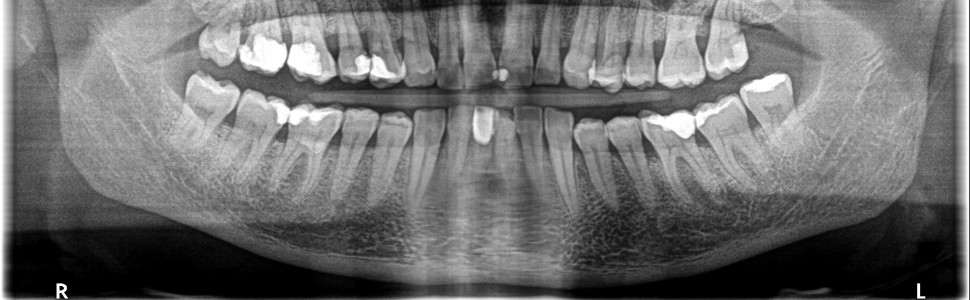

Zębopochodne stany patologiczne zatok szczękowych rozwijają się w zachyłku zębodołowym. Do ich powstania może dojść na podłożu stanów chorobowych miazgi, tkanek okołowierzchołkowych, chorób przyzębia, powikłań leczenia endodontycznego i chirurgicznego. Złotym standardem w ich diagnozowaniu jest tomografia komputerowa wiązki stożkowej. Celem artykułu jest przedstawienie procesu leczenia trzech pacjentów, u których rozpoznano stany patologiczne zatok szczękowych o etiologii zębopochodnej.

Pathological changes of maxillary sinuses develop in the sinus floor. Their development may be prompted by a disease of the pulp, periapical tissues, periodontal disorders, as well as may be due to complications ensuing  during the root canal treatment, or a surgical intervention The gold standard in the diagnosis is cone beam computed tomography. The purpose of this study is to present the treatment process of three patients diagnosed with pathological changes of the maxillary sinuses of odontogenic origin